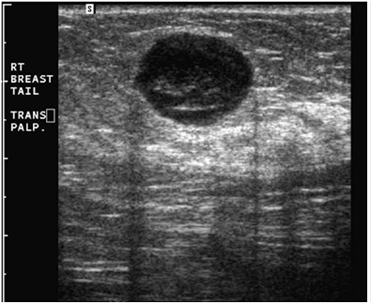

β) Για να διερευνήσουμε τη σύσταση ενός ογκιδίου, συμπαγούς ή κυστικής μορφής (εικόνες 1,2,3) που ψηλαφάται ή φαίνεται μαστογραφικά και να πάρουμε περισσότερες πληροφορίες γι’ αυτό (περίγραμμα, μέγεθος, απόσταση από το δέρμα, αγγείωση).

(Εικόνα 1: Υπερηχογραφική εικόνα ινοαδενώματος (καλοήθους όγκου) του μαστού)